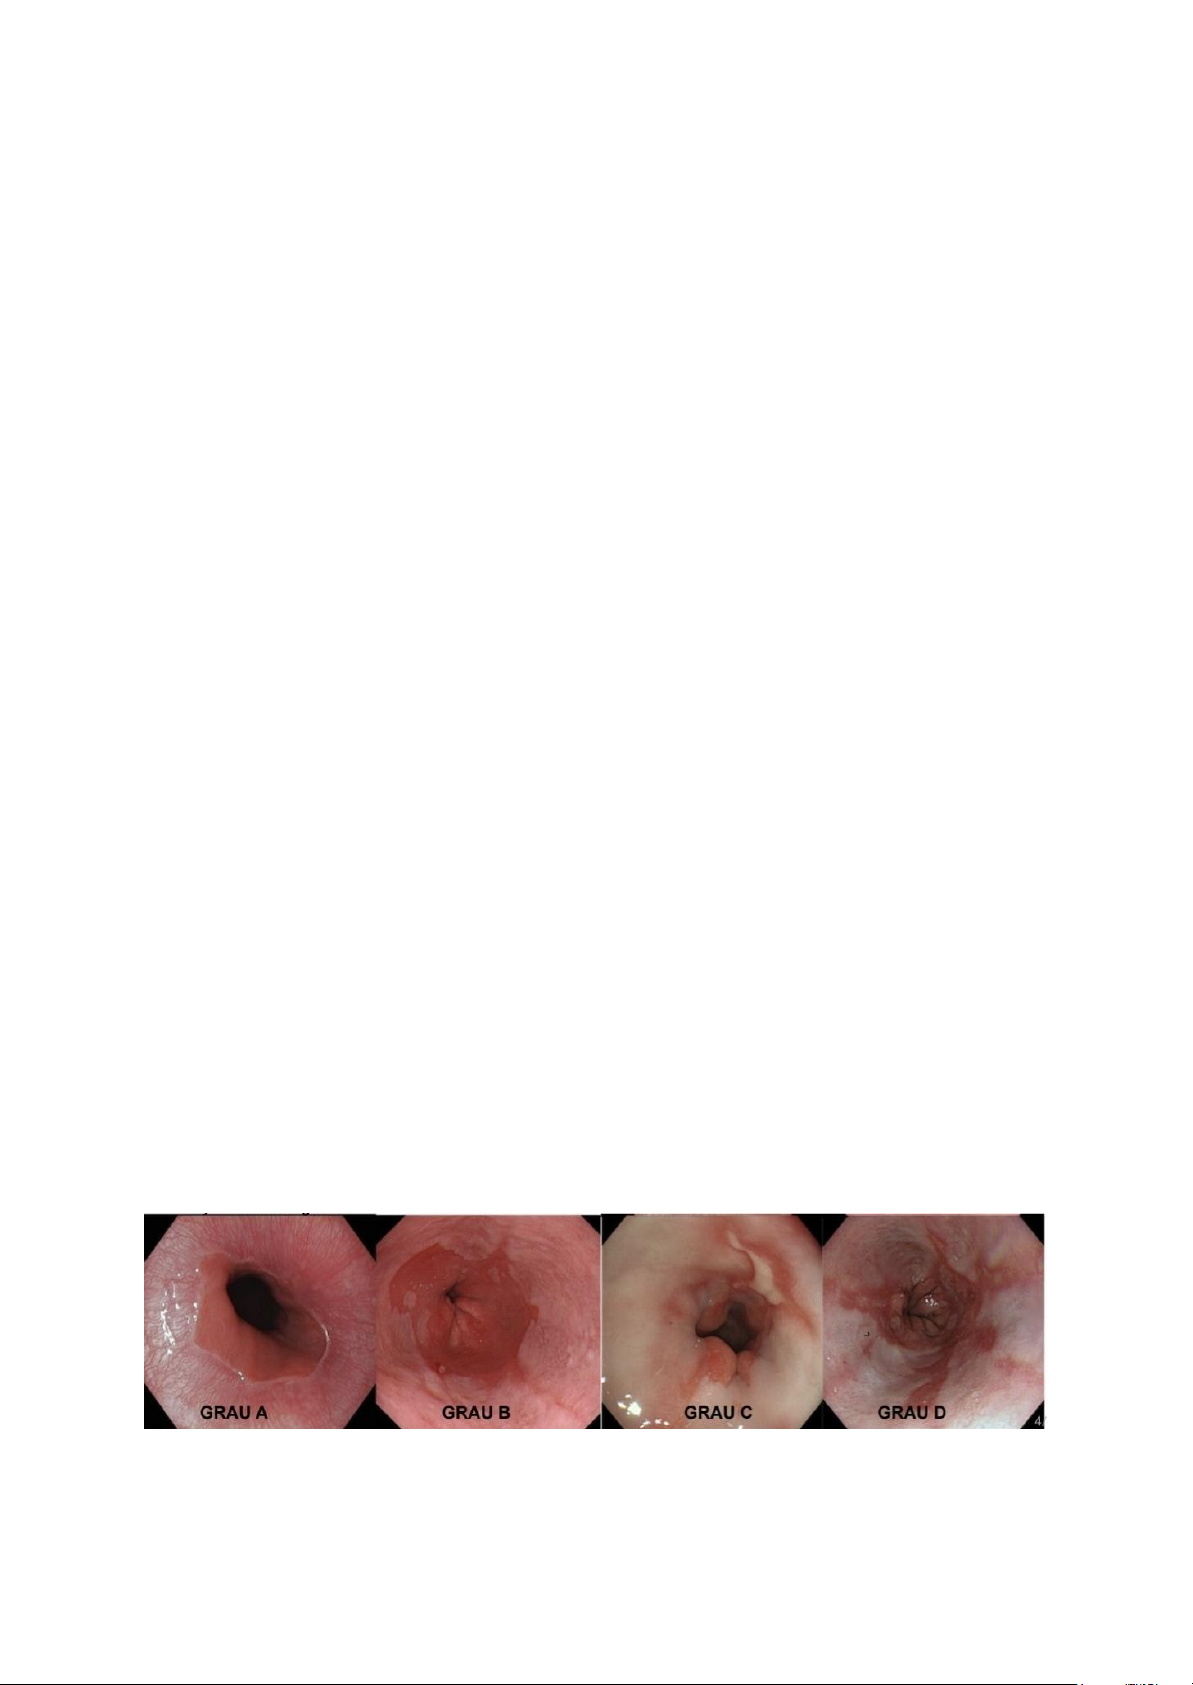

Na esofagite erosiva, o refluxo ácido provoca ruptura visível da mucosa do esôfago distal à

endoscopia digestiva alta. A gravidade dessas lesões é graduada pela classificação de Los

Angeles, que considera a extensão e a confluência das erosões. No grau A, observam-se

pequenas erosões limitadas às pregas da mucosa; no grau B, as erosões tornam-se

maiores, mas ainda não confluentes entre pregas; no grau C, há erosões confluentes

envolvendo menos de 75% da circunferência esofágica; e no grau D, as lesões são

extensas, comprometendo 75% ou mais da circunferência do esôfago. Essa graduação tem

importância prognóstica e terapêutica, especialmente nos graus mais avançados,

associados a maior risco de complicações.